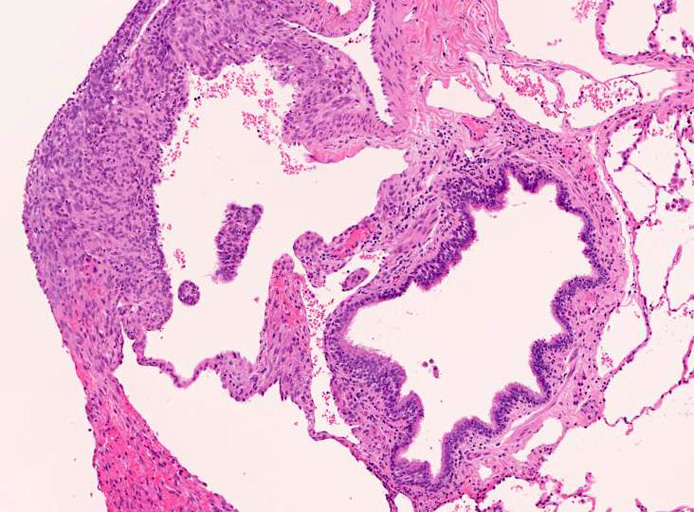

LAMの肺病変

嚢胞周囲または肺血管, リンパ管, 細気管支にそうLAM cellの浸潤, 集簇を特徴とする。LAM cellには2種類が認められ, 小型紡錘形細胞と細胞質の豊富な類上皮様細胞があり, 紡錘型は主に集簇巣の中心に存在し増殖能が高い。 類上皮様LAM cellは辺縁部に多く, 増殖能は低いがHMB45を強く発現している。

嚢胞形成はLAM cellの増殖と関連しており, 細胞が産生するmatrix metalloproteinases(MMPs)による組織破壊によるらしい。